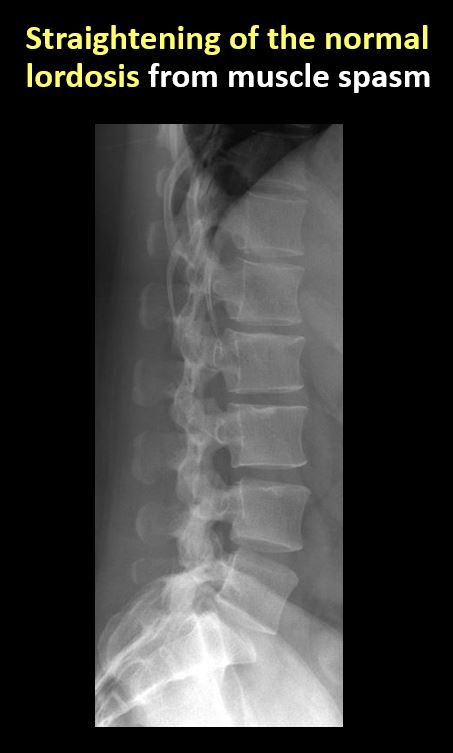

Section 1 Submit Findings CB1239 Findings Technique The thoracolumbar junction and/or the lumbosacral junction is/are not entirely included on the exam. Yes No The exam is over or under penetrated. Yes No The exam is limited by overlying structures, bones or soft tissues, patient positioning, support devices, or motion. Yes No Prevertebral and paravertebral soft tissues The prevertebral or paravertebral soft tissues are abnormal. Yes No Spinal alignment The vertebral bodies are abnormally aligned. Yes No The anterior and posterior vertebral body lines are abnormal or interrupted. Yes No The visualized spinous processes are malaligned or distracted on the AP and/or lateral view(s). Yes No There is reversal or straightening of the normal lordosis or scoliosis of the lumbar spine. Yes No Vertebral bodies, posterior elements and included sacral segments There are more or less than the expected 5 non rib-bearing vertebral bodies. Yes No There is a transitional motion segment at the lumbosacral junction (sacralization of L5 or lumbarization of S1). Yes No There is a fracture or distraction of a vertebral body, transverse or spinous process, or other posterior element. Yes No There is anterior wedging and/or compression of a vertebral body or end plate. Yes No There is an end plate avulsion or other fracture. Yes No There is displacement of a fracture fragment into the soft tissues or spinal canal. Yes No There is lucency or defect of the pars interarticularis from spondylolysis. Yes No There is an abnormality of a pedicle or lamina on the frontal or lateral view. Yes No There is a fracture, erosion, sclerosis, lytic, or blastic lesion of a pedicle or lamina. Yes No There is evidence of a lytic or sclerotic lesion, or disruption of the trabecular pattern of a vertebral body, end plate, or sacrum. Yes No There is a fracture or interruption of the arcuate lines of the sacrum. Yes No There is erosion, sclerosis, narrowing, or other abnormality of a sacral foramen or the SI joints. Yes No There is focal or diffuse abnormal mineralization of the lumbosacral spine. Yes No Disc spaces and facet joints There is distraction or focal widening of a disc space. Yes No There is disc space narrowing with or without erosive or sclerotic changes of the end plates or subchondral bone other than from degenerative change. Yes No There is anterior or posterior spondylolisthesis, subluxation, or rotational abnormality at a disc space. Yes No There is widening, rotational abnormality, or displacement of facets at any motion segment. Yes No There is facet joint narrowing or sclerosis other than from degenerative change. Yes No There is narrowing or encroachment of a neural foramen other than from degenerative change. Yes No There are degenerative changes present that might explain the patient’s symptoms. Yes No Additional soft tissues and bones (lower thorax, abdomen, and pelvis) There is abnormal bowel or bowel gas pattern. Yes No There are gallstones, vascular, renal, pelvic, or other soft tissue calcifications present. Yes No There is free intraperitoneal or retroperitoneal air or other abnormal air in the included chest, abdomen, or pelvis. Yes No The included thoracic spine, ribs, and remainder of the bony pelvis are abnormal. Yes No There is abnormality of the lower chest and/or diaphragm. Yes No There is a foreign body or there are post surgical changes of the bones or soft tissues of the included lower thorax, abdomen, and pelvis. Yes No There is an abnormality or complication of post surgical hardware/device. Yes No N/A There are support lines or tubes in an abnormal position. Yes No Other findings There are other existing conditions that might be contributing to symptoms which can or should be further evaluated non-emergently. Yes No